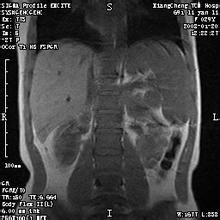

墨菲氏征,為診斷膽囊疾病重要體格檢查實驗,急慢性膽囊炎,膽石症均可出現墨菲氏征陽性。檢查者以左手掌放在患者的右肋緣部,將拇指放在腹直肌外緣與肋弓交界處 (膽囊點)。首先以拇指用中度壓力壓迫腹壁,然後囑患者行深呼吸. 深吸氣時,發炎的膽囊觸及正在加壓的大拇指,引起疼痛,患者因疼痛而突然屏氣,這就是膽囊觸痛征,又稱Murphy氏征陽性,見於急性膽囊炎。

原因 臨床表現墨菲氏征(Murphysign)患者在檢查時,醫生往往叫患者平臥,醫生站在患者右側,左手拇指放在膽囊部位,即右側腹直肌外緣與肋弓交接處(第9肋軟骨尖),...

Murphy 征(Murphy 如發生膽囊穿孔,可有瀰漫性腹膜炎的體徵。